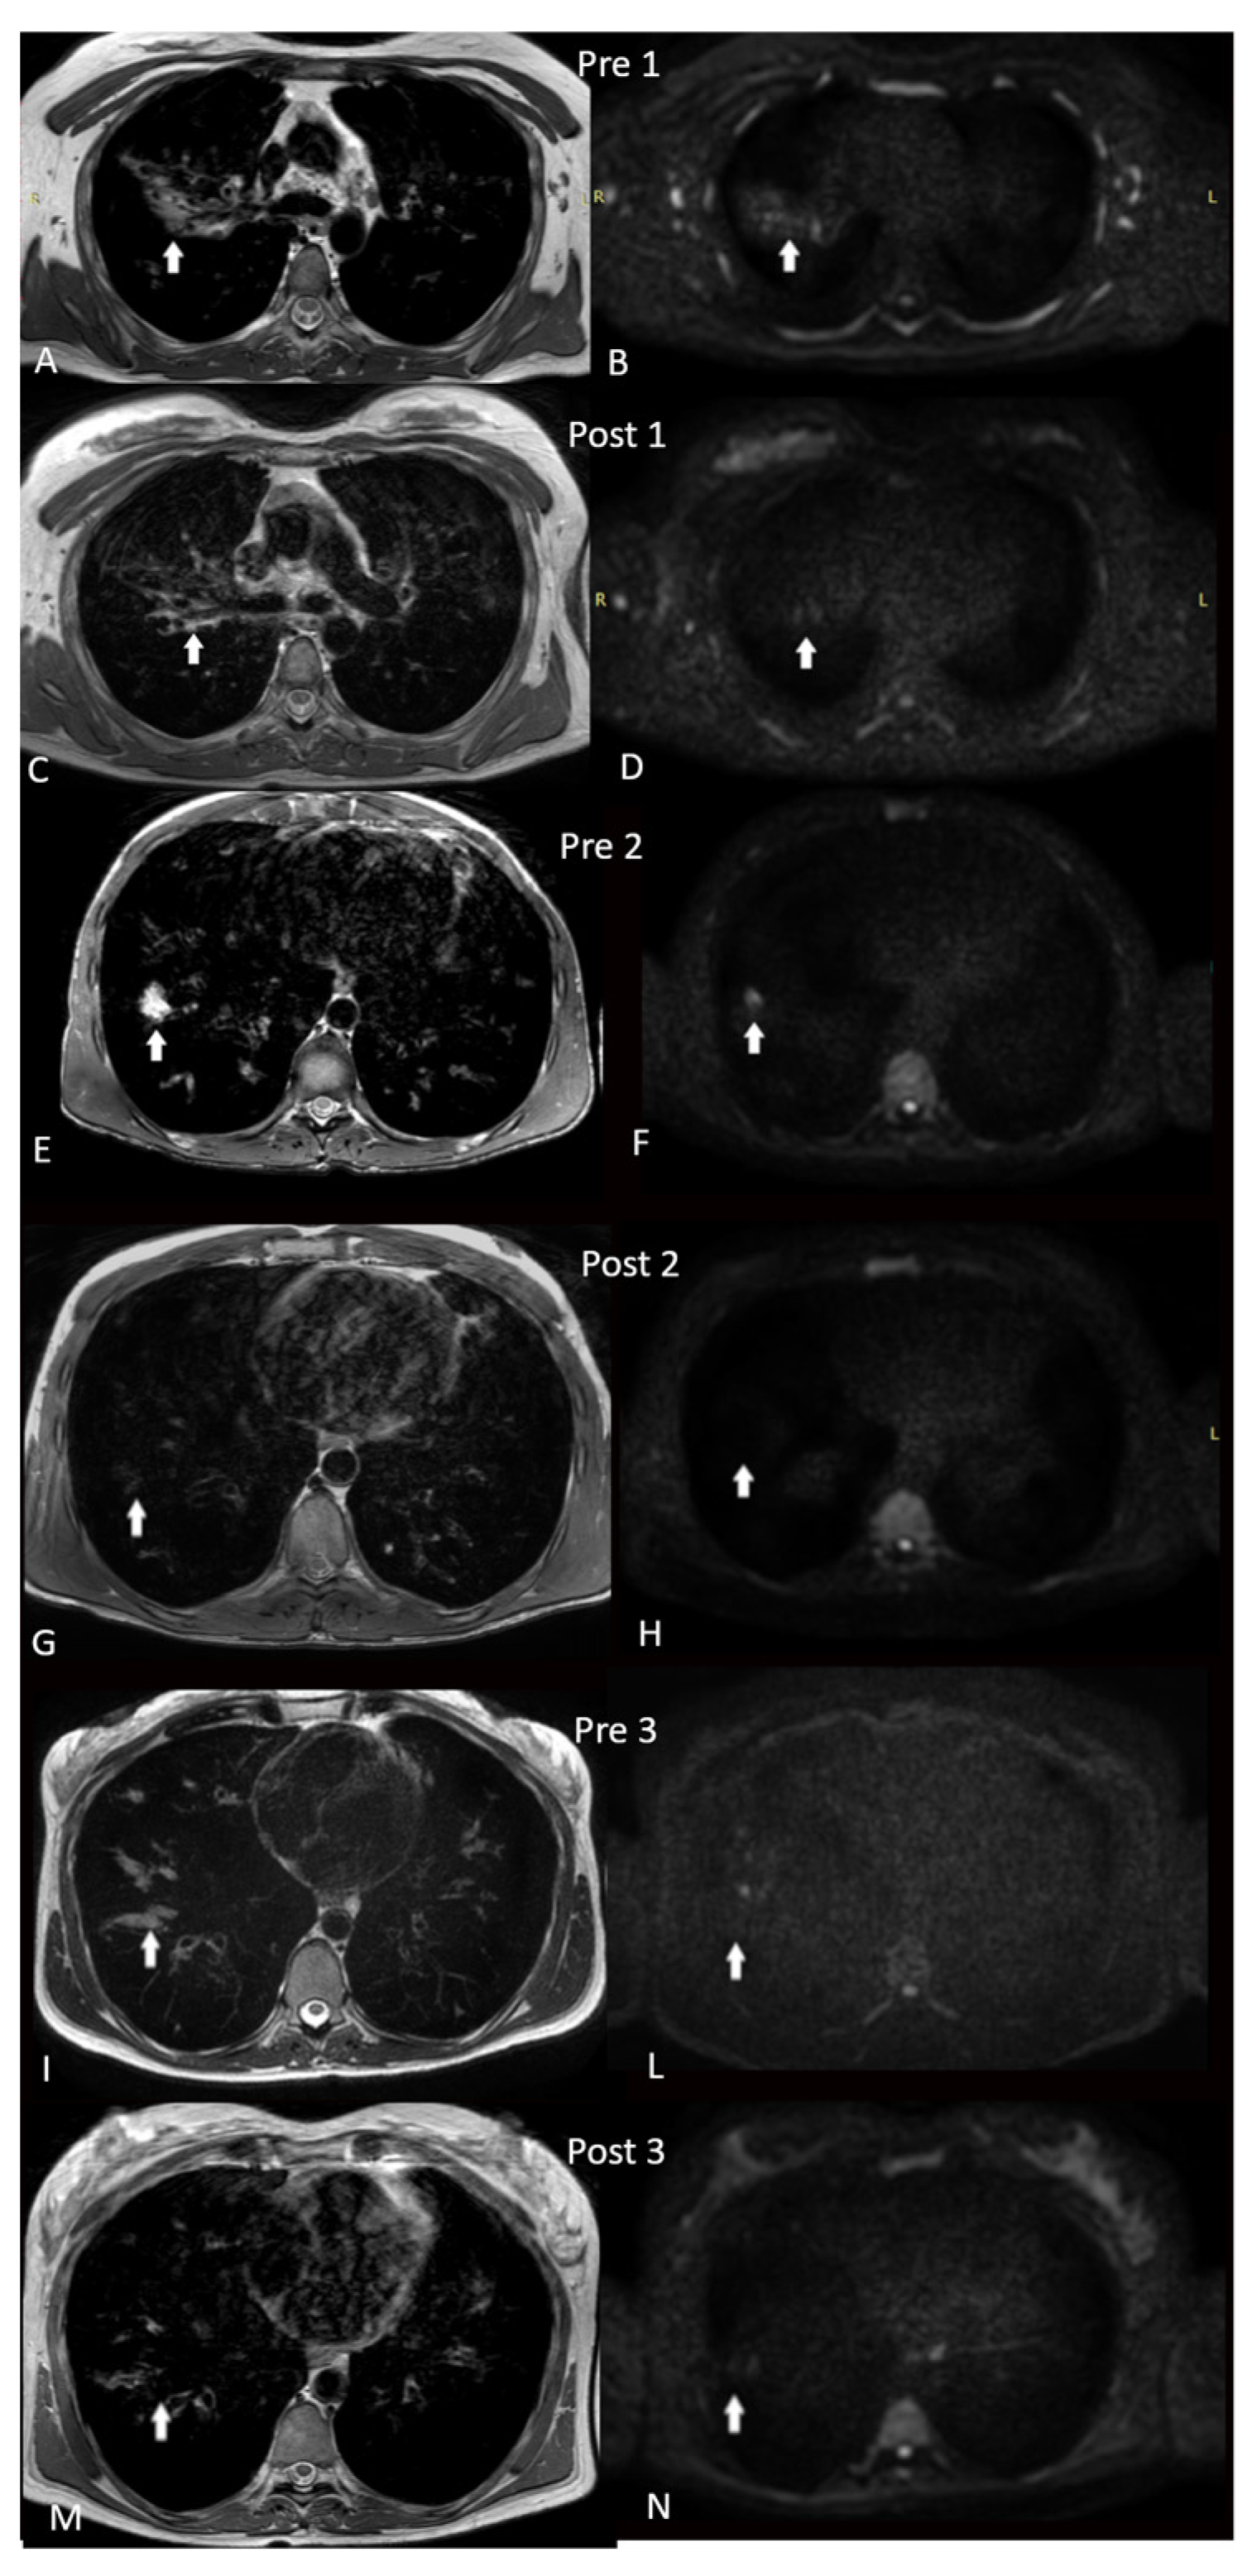

| Characteristics | Baseline | After 3 Months | Baseline | After 3 Months | Baseline | After 3 Months |

|---|---|---|---|---|---|---|

| Subject 1 | Subject 2 | Subject 3 | ||||

| CFTR genotype | F508del/N1303K | F508del/R553Q | F508del/L1065P | |||

| Age (years) | 32 | 43 | 20 | |||

| Sex | F | F | M | |||

| Sweat chloride (mEq/L) | 86 | 53 | 112 | 35 | 123 | 20 |

| FEV1 (%) | 31 | 62 | 36 | 45 | 25 | 47 |

| BMI (kg/m2) | 21.01 | 21.54 | 24.78 | 25.19 | 17.47 | 18.73 |